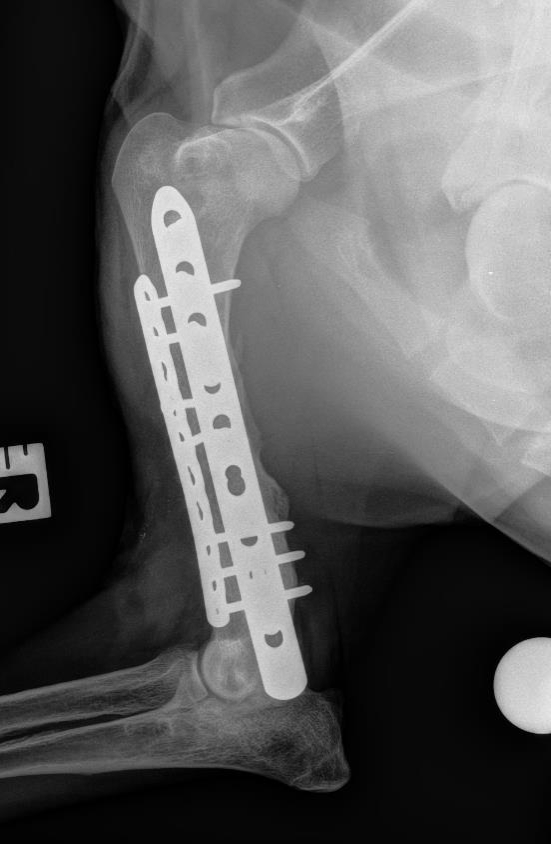

We work to translate therapeutic solutions that address clinical needs in bone regeneration. Our research relies in the use of acellular and cell based complementary strategies to guide stem cell differentiation into osteogenic precursors. Our work has progressed to preclinical models of non-union bone defects and we have planned to start clinical phases with a cell therapy in late 2020. Our core technologies for bone regeneration aim to: